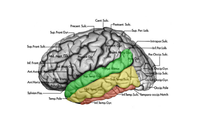

Temporallappen er afgrænset opad til mod lateral fissuren (fissura Sylvii), posteriort mod occipitallappen, postero superiort mod parietallappen, inferiort mod gulvet af fossa crani media, og medialt mod de præpontine cisterne og mod hjernestammen posteriort (Fig. 1). Den mesiale del af temporallappen er beskrevet mere i detaljer i siden om Hippocampus. Husk at gyri og sulci er "koncepter", de er ikke altid kontinuerlige, en gyrus kan således krydses af en sulci og stadig være den samme på den anden side af den pågældende sulci, eller splittes i to parallelle som tilsammen udgør en navngiven sulci. I figurene til høje er angivet såvel de normale gyrus navne, som de mere enkle T1-T5, T6 udgøres af hippocampus.

Lateralsiden af temporallappen udgøres af tre gyri adskilt af to sulci (Fig. 2). Gyrus superior (T1) og gyrus medius (T2) adskilles af sulcus superior, mens gyrus medius og gyrus inferior (T3) adskilles af sulcus inferior.

Den inferiore flade af temporallappen hviler på gulvet af fossa crani media, udgøres af 3 gyri adskilt af to sulci (Fig. 3). Den mest lateral gyrus er gyrus inferior (T3) som er afskilt fra gyrus fusiforme (T4) af en inkomplet sulcus occipito-temporale. Gyrus fusiforme kaldes også gyrus occipito-temporale. Gyrus fusiforme (T4) er adskilt fra gyrus parahippocampale (T5) af sulcus colatteralis. Dybden af sulcus colatteralis prominere ind i temporalhornet af lateralventriklen som prominentia colatteralis.